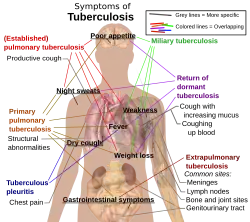

Verschijnselen

Longtuberculose

Als een tuberculose-infectie actief wordt, is dat meestal in de longen, in Nederland in ongeveer 55% van de gevallen. Mogelijke symptomen zijn onder meer pijn op de borst en langdurig hoesten waarbij soms slijm wordt opgehoest. Ongeveer 25% van de patiënten heeft geen symptomen, dat wil zeggen dat ze 'asymptomatisch' blijven.[8] Sommige mensen gaan kleine hoeveelheden bloed ophoesten en in zeer zeldzame gevallen kan de infectie een longslagader aantasten, waardoor een grote bloeding ontstaat.[9] Tuberculose kan een chronische ziekte worden, waarbij uitgebreide littekens in de bovenste longkwabben kunnen ontstaan. De bovenste longkwabben worden meer door tuberculose aangetast dan de onderste longkwabben.[9] De reden daarvoor is niet helemaal duidelijk.[10] Het heeft mogelijk te maken met een betere luchtstroom boven in de longen[10] of met een slechtere afvoer van lymfe uit de bovenste longkwabben.[9]

Extrapulmonale tuberculose

Extrapulmonale tuberculose is tuberculose buiten de longen. In elk orgaan van het lichaam kan tuberculose ontstaan. Haren en nagels zijn daarvan gevrijwaard. In Nederland omvat alleen extrapulmonale tuberculose ongeveer 45% van de patiënten, eveneens 45% van de tuberculose is alleen pulmonaal, dus alleen longtuberculose, en bij de resterende 10% is de ziekte een gemengde vorm. Extrapulmonale tuberculose komt meer bij mensen voor met een verstoord immuunsysteem en bij jonge kinderen. Bij mensen met hiv is dat bij meer dan 50% het geval.[11] Bekende plaatsen voor extrapulmonale infectie zijn onder andere de longvliezen, dan dus tuberculeuze pleuritis, het centrale zenuwstelsel: tuberculeuze hersenvliesontsteking, het lymfevatenstelsel: scrofuloderma van de hals, een huidafwijking, het urogenitaal stelsel, en de beenderen en gewrichten: ziekte van Pott van de wervelkolom. Als de ziekte beenderen betreft, wordt dit ook wel osseuze tuberculose genoemd, een vorm van osteomyelitis.[10] Een ernstiger, wijdverspreide vorm van tuberculose is de gedissemineerde tuberculose, algemeen bekend als miliaire tuberculose.[9] Ongeveer 10% van de gevallen van extrapulmonale tuberculose zijn miliaire tuberculose.

Veel symptomen van de verschillende varianten overlappen elkaar, terwijl andere symptomen specifiek voor bepaalde varianten zijn. Er kunnen verschillende varianten tegelijkertijd aanwezig zijn.